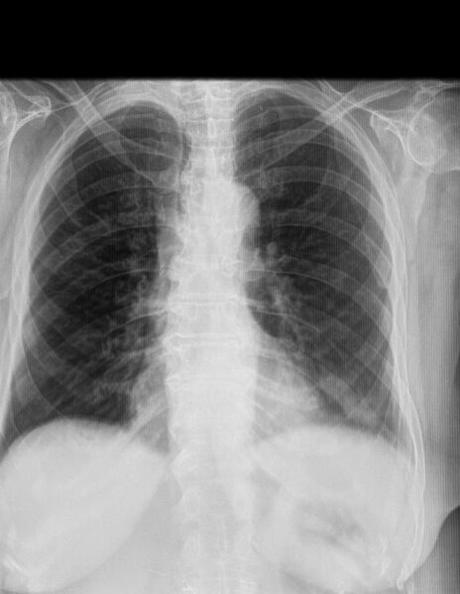

LA PROYECCION RADIOLOGICA OBTENIDA NOS MUESTRA LOS SIGUIENTES HALLAZGOS:

-Tejidos blandos, con densidad conservada, simétricos, sin evidencia de alteraciones.

-Estructuras óseas, sin evidencia de lesiones líticas, blásticas o perdida de la contigüidad. Con una vertebral central, con presencia de osteofitos marginales, con tendencia la formación de espículas.

-Vía aérea permeable.

-Mediastino, sin alteraciones. Botón aórtico, con calcificaciones.

-Corazón, con índice cardiotorácico menor a 0.5.

-Hilios pulmonares, con adecuada densidad. Existiendo en hilio pulmonar izquierdo, la presencia de imagen redondeada, regular, bien definida que mide 7 × 5 mm.

-Trama bronco-vascular, conservada.

-Campos pulmonares, con opacificación reticular difusa, a nivel de hilio pulmonar izquierdo, con presencia de imagen redondeada, regular, bien definida que mide 7 × 5 mm.

-Recesos cardiofrénicos y costofrénico sin alteraciones.

OPINIÓN RADIOLÓGICA:

EN EL PRESENTE ESTUDIO RADIOGRÁFICO, CON DATOS DE NEUMOPATÍA CRÓNICA INTERSTICIAL.

PULMÓN IZQUIERDO, EN TOPOGRAFÍA BILIAR, CON PRESENCIA DE IMAGEN SUGERENTE DE GANGLIO VS NÓDULO O GRANULOMA CALCIFICADO.

CAMBIOS OSTEODEGENERATIVOS Y ATEROESCLEROSIS.

CORRELACIONAR CON DATOS E HISTORIA CLINICA DEL PACIENTE